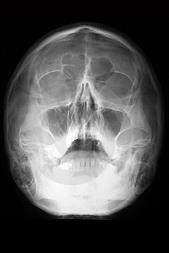

Posteroanterior projection

purpose of posteroanterior projection

Used to evaluate trauma; demonstrates frontal sinuses, orbit and nasal cavity